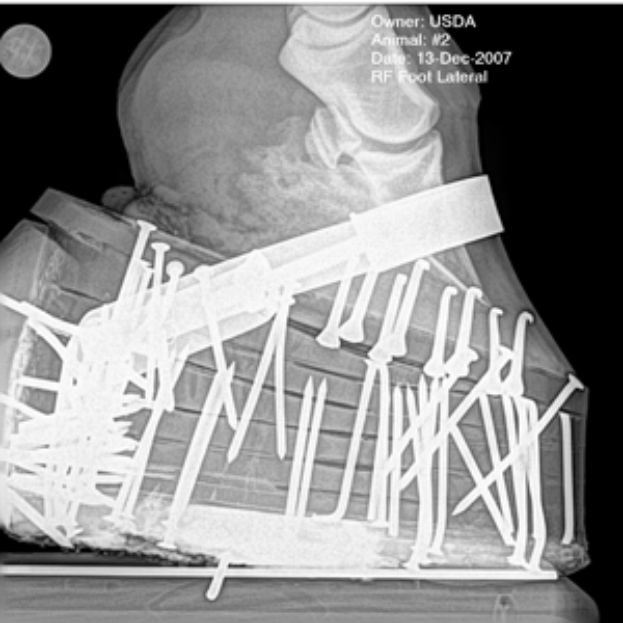

Ein Röntgenbild eines Mannes mit einem sichtbaren Bruch im Knöchel, der mit einem Verband umwickelt ist, und Text oben und unten auf dem Bild.

Hamburger SV-Mittelfeldspieler Albert Sambi Lokonga fällt nach einer Sprunggelenksverletzung mehrere Wochen aus. Der 26-Jährige musste am 9. Februar 2026 im Auswärtsspiel gegen den 1. FC Heidenheim verletzt vom Platz gehen. Spätere Untersuchungen bestätigten einen Außenbandriss im linken Knöchel.